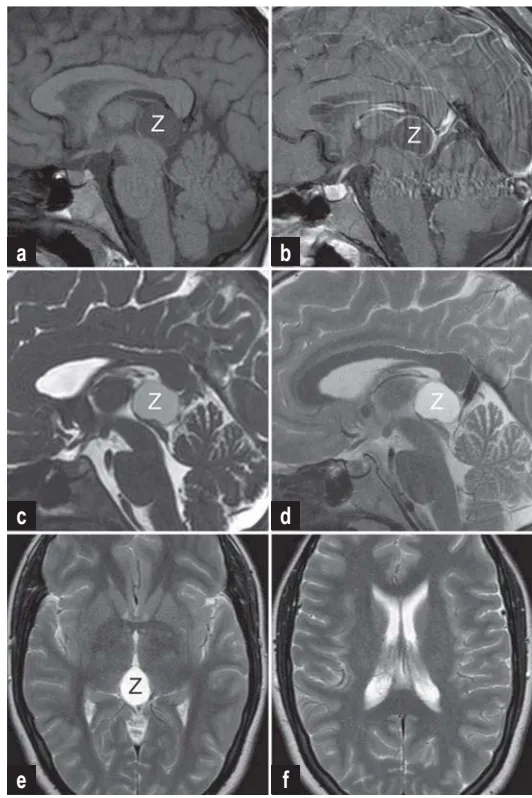

通过MRI,松果体囊肿通常表现为球形结构,内部低信号,边缘有强化。最佳诊断序列包括T1加权、CISS序列和流动敏感序列,以全面评估囊肿与导水管的关系。

a)平扫T1加权像显示松果体区低信号占位病变

b)增强扫描显示典型的囊肿膜球形强化

c,d)矢状位CISS和T2加权像显示导水管入口轻度狭窄

e,f)T2加权轴位图像显示狭窄的第三脑室和未扩大的侧脑室